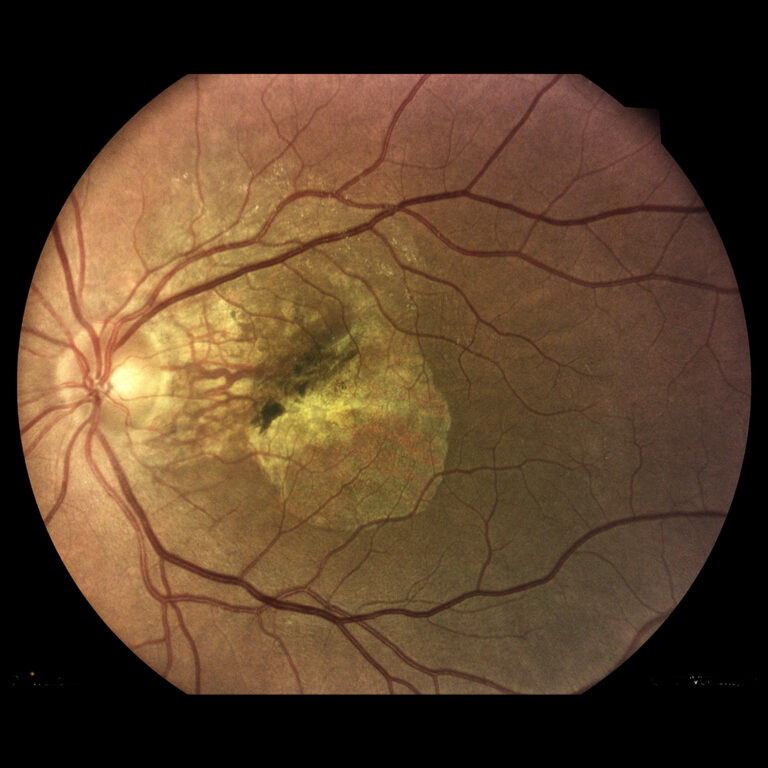

Vekom podmienená makulárna degenerácia (VPMD)

Vekom podmienená makulárna degenerácia je velmi závažné ochorenie sietnice a je najčastejšou príčinou straty zraku u starších ľudí. V rozvinutých krajinách je dokonca najčastejšou príčinou praktickej slepoty.

Pri makulárnej degenerácii dochádza k postihnutiu tzv. žltej škvrny (centrálnej časti očnej sietnice). Ochorenie sa vyskytuje v dvoch formách - suchá a vlhká, pričom "vlhká" forma postupuje veľmi rýchlo a dokáže zrak zničiť behom niekoľkých týždňov či mesiacov. Včasným rozpoznaním tejto choroby a včasnou diagnostikou je možné ztratu zraku zastaviť. Ľudia nad 50 rokov by preto mali pravidelne podsupovať jednak takéto skríningy očného pozadia, ako aj komplexné očné vyšetrenie.

- infračervené mapy zvýrazňujúce svetlé a červené lézie/poškodenia